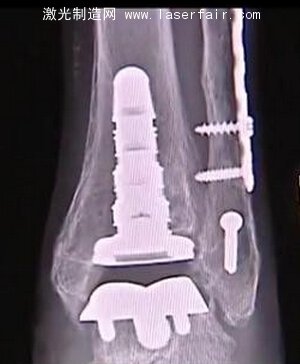

德州醫(yī)生成功完成3D打印踝關(guān)節(jié)置換手術(shù)

一個(gè)名叫Bettye Dube的女人應(yīng)當(dāng)感謝3D打印技術(shù)應(yīng)用帶給她的幫助。Dube當(dāng)初在牙買加度假時(shí)不幸跌倒,導(dǎo)致她的腳踝粉碎性骨折。在打了幾個(gè)月的石膏,并進(jìn)行廣泛的物理治療后,她的兩個(gè)腳踝變得不一樣了。于是一個(gè)朋友建議她去找Marvin Brown醫(yī)生。Brown醫(yī)生是足部、踝部和小腿關(guān)節(jié)置換的專家,他的辦公地點(diǎn)在德克薩斯州的San Antonio。Brown認(rèn)為Dube需要做踝關(guān)節(jié)置換手術(shù)。

Brown醫(yī)生精通最新的技術(shù),他決定使用一個(gè)相對較新的手術(shù)方法。他使用一截最先進(jìn)的3D打印假肢“inbone”置換了Dube的整個(gè)腳踝。

3D打印能夠根據(jù)Dube的個(gè)人特征為其量身定做特殊的腳踝,效果要比過去的一些傳統(tǒng)的踝關(guān)節(jié)置換好得多。雖然Dube的腳踝不能100%地恢復(fù)到她跌倒以前的狀況,而且她再也不能穿高跟鞋,手術(shù)仍然是令人難以置信的成功。

在踝關(guān)節(jié)置換中的3D打印部分可以保持大約10年,只要Dube遵循醫(yī)生的囑咐,注意她的重量,并且穿減震的鞋子。